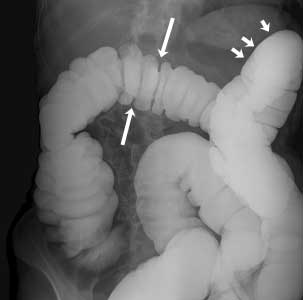

Courtesy of Intermountain Medical Imaging, Boise, Idaho. All rights reserved.

This image shows a normal colon filled with barium. The barium shows up as white on the image. The arrows point to the normal curves of the colon.